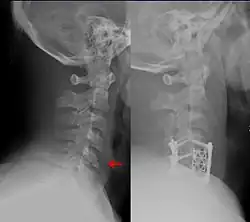

Cervical Spine Clearance

There are two main algorithms, the Canadian C-spine rule and NEXUS, which are used to decide who requires cervical spine imaging via CT scan[6] after blunt trauma, and who can be cleared without imaging.[4] The Canadian C-spine rule appears to have greater sensitivity and specificity (i.e. fewer false positives and false negatives).[17] However, following either rule is reasonable.

If the chosen decision rule (NEXUS or Canadian C-spine) is negative, or if cervical spine imaging is negative, the cervical collar can be removed if the patient does not have significant midline tenderness and can move the neck 45 degrees to both sides.[6] If a patient cannot do both, the collar should be replaced and additional imaging or follow-up should be pursued depending on facility guidelines.[6]

There are multiple devices that can be used in addition to avoiding maneuvers or activities that move the spine.[8][18] Long-term cervical spine immobilization in patients with cervical spine fracture who did not undergo surgery can be performed using a long-term cervical collar (Miami J,[6][8] Philadelphia,[8] or Aspen[8]) or halo traction device.[8][12] When using a traction device such as the halo to hold the spine in place while it heals, this is called closed reduction, as opposed to a surgery which is termed open reduction with internal fixation (ORIF).[18] In general, the halo traction device is preferred for unstable fracture, while the cervical collars are used for neck sprain, stable fracture, or after surgical fixation.[8] Soft cervical collars do not restrict head movement and are more so used for comfort.[8] The sternal occipital mandibular immobilizer (SOMI) can also be used to provide support for cervical spine sprain, stable fracture, or postoperative support.[8]